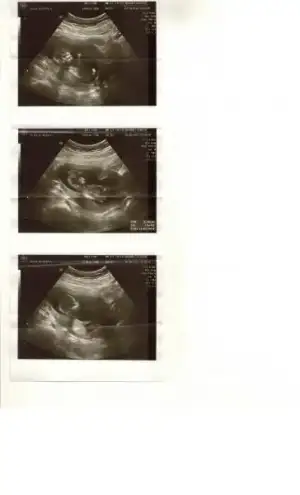

Merhabalar, ilk defa yazıyorum rica etsem yukardaki ultrason görüntüsünü yorumlayabilecek tecrübeli annelerin görüşlerini bekliyorum.. ilk hamileliğim 12+1'im . doktor ultrasonda yorum yapmaktan kaçındı önce büyük ihtimalle kız dedi daha sonra bir çıkıntı var emin değilim %50-50 ye çevirdi olayı.. yorumlayabilecek arkadaşların katkılarını bekliyorum teşekkür ederim

Merhabalar, ilk defa yazıyorum rica etsem yukardaki ultrason görüntüsünü yorumlayabilecek tecrübeli annelerin görüşlerini bekliyorum.. ilk hamileliğim 12+1'im . doktor ultrasonda yorum yapmaktan kaçındı önce büyük ihtimalle kız dedi daha sonra bir çıkıntı var emin değilim %50-50 ye çevirdi olayı.. yorumlayabilecek arkadaşların katkılarını bekliyorum teşekkür ederim

canım çok bişey belli değil ama erkek gibi

Merhabalar, ilk defa yazıyorum rica etsem yukardaki ultrason görüntüsünü yorumlayabilecek tecrübeli annelerin görüşlerini bekliyorum.. ilk hamileliğim 12+1'im . doktor ultrasonda yorum yapmaktan kaçındı önce büyük ihtimalle kız dedi daha sonra bir çıkıntı var emin değilim %50-50 ye çevirdi olayı.. yorumlayabilecek arkadaşların katkılarını bekliyorum teşekkür ederim

ayol bu erkek

artık bi sürü foto görmekten az çok tahmin edebiliyoruz :)

Eki Görüntüle 823960

Merhabalar, ilk defa yazıyorum rica etsem yukardaki ultrason görüntüsünü yorumlayabilecek tecrübeli annelerin görüşlerini bekliyorum.. ilk hamileliğim 12+1'im . doktor ultrasonda yorum yapmaktan kaçındı önce büyük ihtimalle kız dedi daha sonra bir çıkıntı var emin değilim %50-50 ye çevirdi olayı.. yorumlayabilecek arkadaşların katkılarını bekliyorum teşekkür ederim

%99 erkeeeek

13+3 günlük

yorumlarınızı beklıorum kızlar.ben cıkıntı göremedim ayak o sanırım :)) cıkıntıya benzeyen kısım

13+3 günlük

yorumlarınızı beklıorum kızlar.ben cıkıntı göremedim ayak o sanırım :)) cıkıntıya benzeyen kısım

onun altinda bir nub göruntusu var kiz olasiligi var onunlada